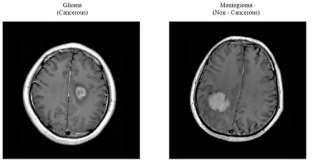

The tumor-affected area of the brain is shown in Fig- 1, which additionally determines the precise position of the infectionwithinthebrain.